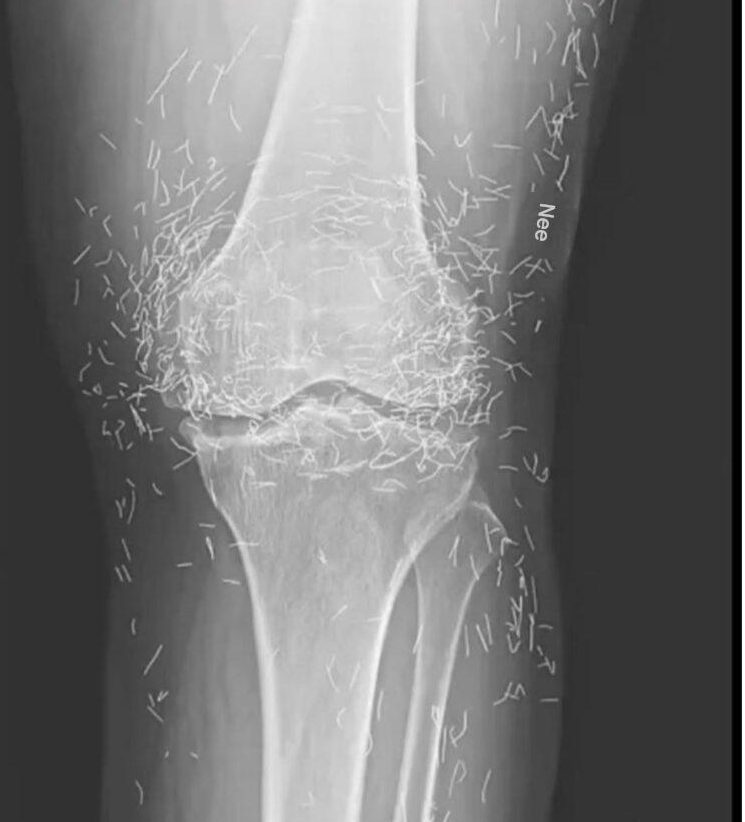

Als Ärzte ein Röntgenbild der Knie einer älteren Frau untersuchten, die unter starken Gelenkschmerzen litt, entdeckten sie eine Goldgrube: Hunderte winziger goldener Akupunkturnadeln waren in ihrem Gewebe zurückgeblieben.

Die 65-jährige Südkoreanerin war zuvor an Arthrose erkrankt, eine Erkrankung, bei der Knorpel und Knochen in den Gelenken abgebaut werden, was Schmerzen und Steifheit verursachte. Als Schmerzmittel und Entzündungshemmer die Knieschmerzen jedoch nicht linderten und lediglich Magenbeschwerden auslösten, wandte sie sich der Akupunktur zu, wie Ärzte vergangene Woche im New England Journal of Medicine berichteten.

Während der Akupunkturbehandlung der Frau wurden die Nadeln, die vermutlich aus Gold bestanden, absichtlich in ihrem Gewebe belassen, um eine kontinuierliche Stimulation zu gewährleisten, heißt es in dem Bericht.

Es könnte auch die Beurteilung eines Röntgenbildes durch den Arzt erschweren. „Die Nadeln können Teile der Anatomie verdecken“, sagt Guermazi.